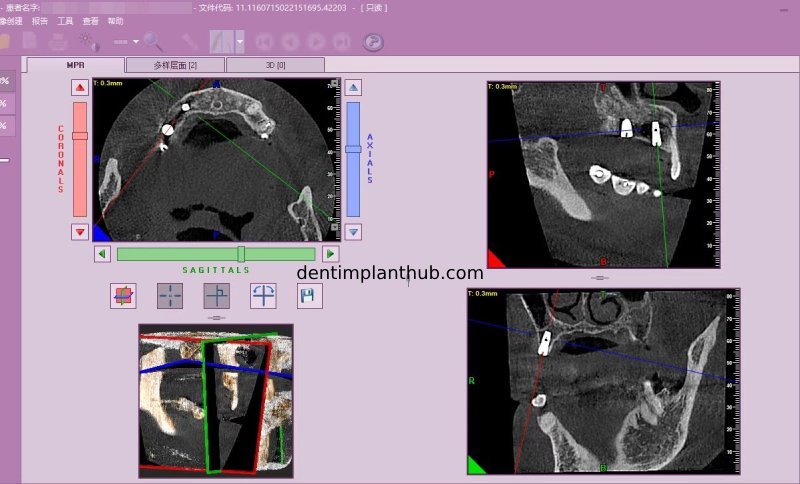

Screenshot of repeat CT on 7/1/25